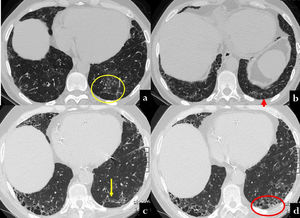

Evans et al. postulated that excessive production of MUC5B by stem cells that attempt to regenerate injured bronchiolar and alveolar epithelia may disrupt normal developmental pathways and enhance normal reparative mechanisms in the distal lung.113 This was recently demonstrated by histological, CT, and micro-CT analyses of eight explanted lungs or lobes with ILAs from six donors.124 The authors drew a correlation between the findings of ex vivo CT scans and the histological samples, reporting scarcely affected or near-to-normal portions of parenchyma with paraseptal fibrosis in most cases (78 %) and lymphocytic inflammation (86 %). Of particular interest is the concept of ‘paraseptal’ fibrosis, which has been described to originate from the periphery of the secondary lobule and moving inward to the centrolobule. This has already been described in surgical specimens by Colby et al. and, more recently, by Johkoh et al.140,141 The early changes in UIP patterns are characterised by an admixture of dilatation of the terminal airway and periacinar fibrosis. The peripheral acinar distribution is typical of the less fibrotic areas and can be discerned as emanating from the septa and the pleura around the bronchovascular structures.140 The corresponding imaging aspect is the reticulation, which assumes an ‘arciform aspect’ when it is subpleural or is polygonal shaped when it is far from the pleura (Fig. 6). This periacinar pattern may be identifiable in transbronchial cryobiopsy samples (Fig. 7a,b). The periacinar distribution may still be discernible on follow-up CT scans even when a typical UIP pattern appears (Fig. 7c,d). Verleden et al. also found that the opacities in or near the interlobular septa are thicker and, in more advanced stages, associated with aberrant airway-like structures that gradually fill the entire secondary lobule with progressive loss of alveolar epithelium.124 A UIP-like pattern has been described in association with pleuroparenchymal fibroelastosis (PPFE), which shows a clearly worse prognosis in comparison with other phenotypes of PPFE.142,128 While elastin fibres in the normal lung contribute to normal lung compliance and elastic return, in ILDs, overexpression of elastin leads to scarring and impaired lung function.129 An increased elastin burden has been documented in the proliferative phase of DAD and in UP as well, suggesting that it may contribute to the alveolar mechanical dysfunction and remodelling both in acute and chronic ILDs.130 In the UIP pattern, the elastin deposition is observed along the interalveolar and alveolar septal wall, and its degree correlates with the disease progression and 5-year survival.131 PPFE is also one of the most representative findings in telomere diseases, being part of a constellation of atypical or discordant findings on pathological and radiological assessments.132 The future horizons of imaging are represented by a further improvements in the resolution and the identification of coarseness. Ultra-high-resolution photon-counting CT allows more precise depiction of the lung parenchyma, with a sharper delineation of the subtle features of nonfibrotic and fibrotic ILDs.133 Finally, the implementation of deep learning algorithms for assessment of IPF represents an emerging tool that may address several unmet needs both in the research setting and in clinical practice.134,143

CT scan at baseline (a,b) and twelve years later (b,c) in a 70 year old male, with history of polymiositis and dermatomyositis. In the first CT, scattered nodular ground glass opacities are present in both lower lobes (a). Moreover, some linear opacities with an arciform aspect are visible beneath the pleura, mainly in the left lobe (a, yellow circle; b, red arrow). After twelve years, the patient showed UIP patern characterized by ttraction bronchiectasis and honeycombing along the arciform lesion of the prior exam (c, yellow circle; d, red circle).

Clinical/radiological message: CT scan arciform subpleural lines may represent the periacinar distribution in UIP.